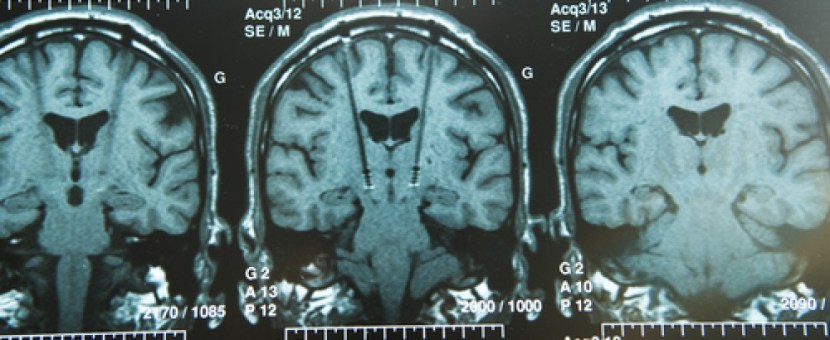

Brain imaging of iron (using transcranial sonography and magnetic resonance imaging (MRI)) has also demonstrated a strong correlation between iron levels in the substantia nigra region and Parkinson’s disease severity/duration (Click here and here to read more on this).

In addition, there was less atrophy (shrinkage) in the brains of those patients treated with PBT2 when compared to control brains, 2.6% and 4.0%, respectively (based on brain imaging). The company is tracking measures of brain volume and cognition in a 12 month extension study. It could be interesting to continue that follow up long term to evaluate the consequences of long term use of this drug on Alzheimer’s disease – even if the effect is minimal, any drug that can slow the disease down is useful and could be used in conjunction with other neuroprotective medications.